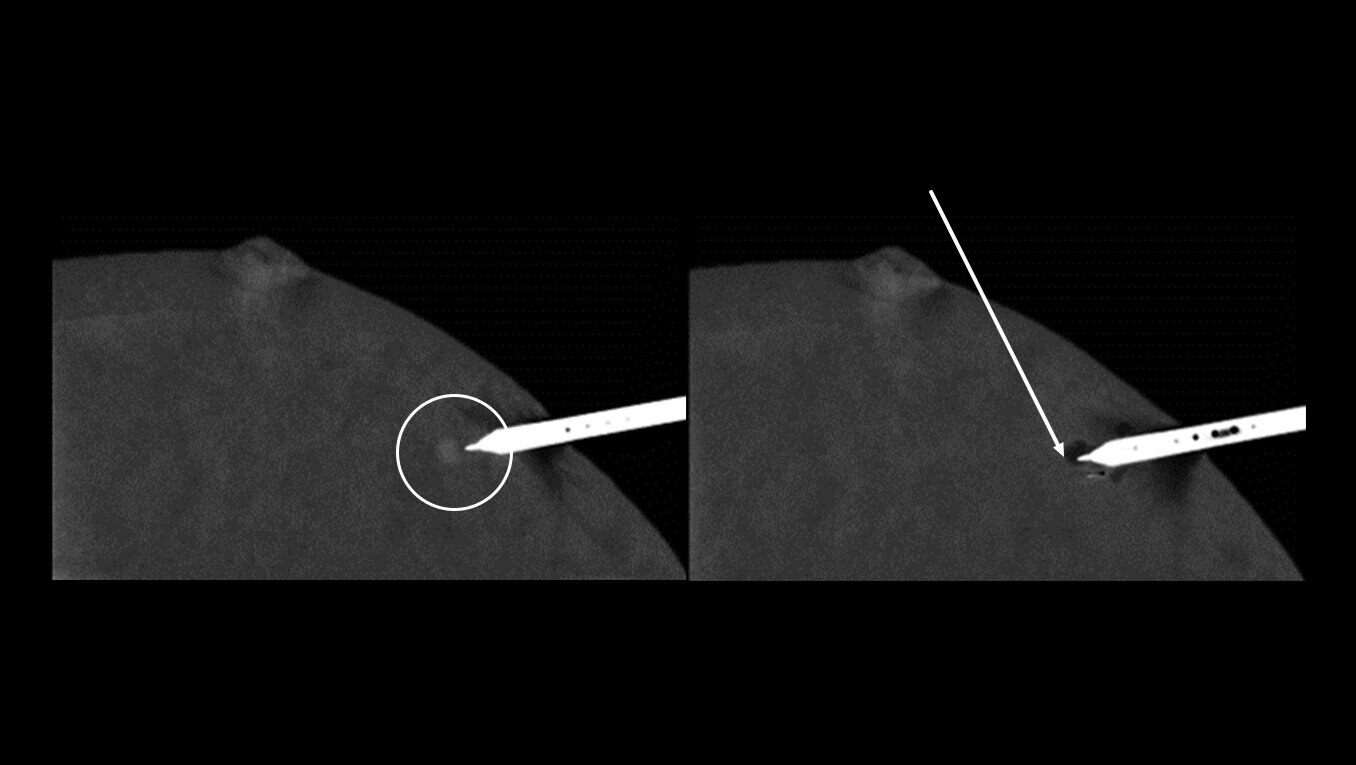

Avoid the challenges of seeking correlating lesions in MRI. CEM allows you to see lesions clearly and sample with certainty with the same image guidance.

With high sensitivity and specificity, CEM helps drive accuracy in biopsy. It allows you to clearly target suspicious areas by correlating lesion locations already identified in your patient’s diagnostic enhanced mammogram.

No more delays waiting for MRI availability or enduring lengthy 60-90 minute5 MRI-guided breast biopsy procedures. CEM guided biopsy can be performed within 15 minutes from first image to clip placement image6. A shorter biopsy lead time and quicker biopsy procedure may speed up a definitive diagnosis and faster path to treatment.